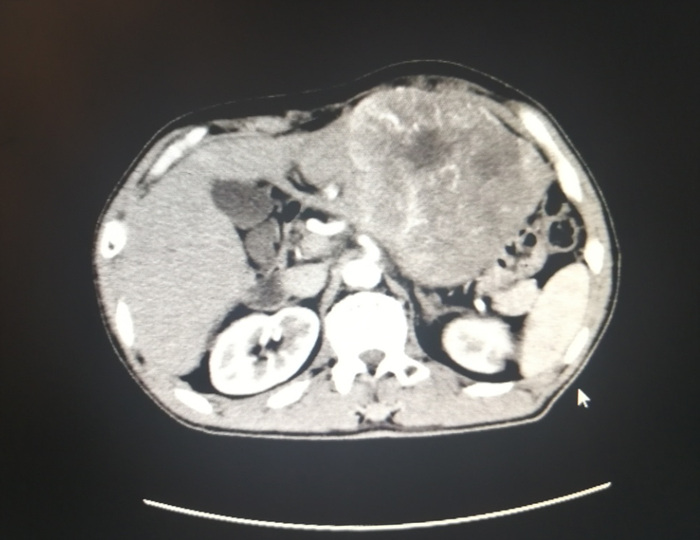

该男性患者左上腹部出现肿物已有一段时间,因不痛不痒,所以没有太在意,近日在进食时感觉上腹部常有饱胀不适,偶尔伴有恶心干呕,遂入住我院外科一区。入院后行体查发现左上腹扪及一肿物,大小约13.0×12.0cm,质地硬,轻压痛,活动度欠佳;经腹部CT及相关辅助检查确诊患者为肝左叶巨大恶性肿瘤。

10月26日,在普外科、手术麻醉科的精心配合下,范海鹰副主任、任伟耀副主任医师在手术室经过近5小时奋战,完整地切除左半肝巨大肿瘤,重达1.5公斤,术程顺利,术中出血少,患者术后恢复良好,病理结果为中-低分化肝细胞癌。